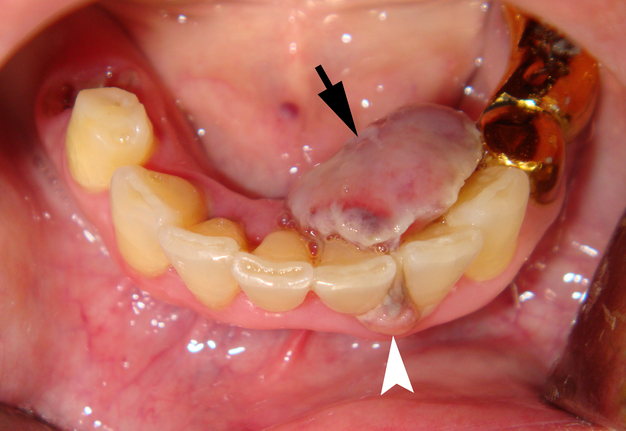

Clinical examination revealed the presence of a neoplasm on the lingual side of the alveolar process of the mandible that had grown vestibularly between the left central and lateral incisors (Fig 1). The neoplasm was mushroom-shaped, pale pink in color, elastic upon palpation, and had a pedicle. The mucosa adjacent to the neoplasm is unchanged in color and structure. The neoplasm measured 1.8 x 1.1 x 1.2 cm at the lingual aspect of the lower teeth and 0.34 x 0.38 cm at the vestibular aspect.